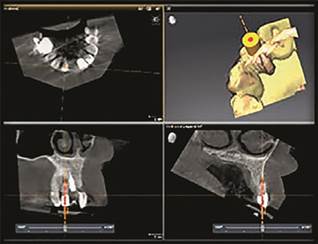

Εικ. 1. Η αλληλεπίθεση του ψηφιακού αποτυπώματος επάνω στην απεικόνιση CBCT με μία σχεδιασμένη διαδρομή.

Σχεδιασμός της διαδρομής του οδηγού διαδρομής με το λογισμικό CBCT (α).

Μία σχεδιασμένη διαδρομή στην απεικόνιση CBCT (β).

Απεικόνιση του ψηφιακού αποτυπώματος στο λογισμικό ψηφιακής οδοντιατρικής (γ).

Η διαδικασία ξεκινά με τη λήψη μιας σάρωσης CBCT για την αναγνώριση και την εξέταση των ριζικών σωλήνων. Η τρισδιάστατη απεικόνιση της CBCT συχνά αποκαλύπτει ριζικούς σωλήνες οι οποίοι δεν μπορούν να παρατηρηθούν στις συμβατικές δισδιάστατες οπισθοφατνιακές ακτινογραφίες. Τέτοια παραδείγματα είναι ο συχνά υπεκφεύγων δεύτερος εγγύς-παρειακός ριζικός σωλήνας των γομφίων της άνω γνάθου ή οι δεύτεροι ριζικοί σωλήνες που παρατηρούνται στους τομείς και τους προγομφίους της κάτω γνάθου. Όταν αναπτύσσεται ενασβεστίωση των ριζικών σωλήνων, αυτή συνήθως ξεκινά στον πολφικό θάλαμο και κινείται ακρορριζικά. Όταν ένα δόντι υφίσταται ασβεστούχο μεταμόρφωση, συχνά οι ριζικοί σωλήνες δεν είναι ορατοί στο μυλικό και μέσο τριτημόριο της ρίζας, αλλά είναι ορατοί στο ακρορριζικό τριτημόριο. Όταν αυτοί οι ριζικοί σωλήνες εξετάζονται σε μία απεικόνιση CBCT, παρ’ ότι δεν είναι ορατοί, μπορεί να φανταστεί κανείς μία ευθεία οδό από τον πολφικό θάλαμο μέχρι το ακρορριζικό τριτημόριο του ριζικού σωλήνα. Σήμερα, υπάρχουν διαθέσιμα προγράμματα για υπολογιστές που μπορούν να αναπαραγάγουν αυτήν την οδό διά μέσω της ενασβεστίωσης προς τον παραμένοντα ριζικό σωλήνα. Το SICAT Endo προσφέρει μία τέτοια υπηρεσία.

Αφού λάβετε την απεικόνιση CBCT, πάρτε ένα ψηφιακό αποτύπωμα του ίδιου τόξου. Κάντε αλληλεπίθεση των δεδομένων του ψηφιακού αποτυπώματος επάνω στα δεδομένα της σάρωσης CBCT. Επιλέξτε τέσσερα κοινά σημεία και στα δύο τόξα για να ευθυγραμμίσετε τις πληροφορίες. Αφού γίνει το ταίριασμα και η συγχώνευση, η προηγουμένως φανταστική οδός μπορεί να μετρηθεί με ακρίβεια στο λογισμικό από την κορυφή του φύματος μέχρι τον υπολειμματικό ριζικό σωλήνα. Αυτές οι ψηφιακές πληροφορίες είναι έτοιμες να χρησιμοποιηθούν για τη δημιουργία ενός οδηγού. Το επόμενο βήμα είναι να χρησιμοποιηθεί το λογισμικό για τη σχεδίαση ενός άκαμπτου νάρθηκα ο οποίος εφαρμόζει επάνω στη μασητική η την κοπτική επιφάνεια. Ο νάρθηκας πρέπει να εκτείνεται πέραν του θεραπευόμενου δοντιού και προς τις δύο κατευθύνσεις. Αυτή η πρόσθετη διάσταση προσφέρει σταθερότητα κατά την έδραση του νάρθηκα. Στον νάρθηκα σχεδιάζεται ένας χώρος επάνω από το δόντι για να συγκρατήσει έναν μεταλλικό σωληνίσκο 5 mm. Στον υπολογιστή, ευθυγραμμίστε τον σωληνίσκο με την προτεινόμενη διαδρομή. Κατασκευάστε τον νάρθηκα σε έναν τρισδιάστατο εκτυπωτή. Αφού ολοκληρωθεί η κατασκευή του, εισάγετε τον σωληνίσκο στον νάρθηκα. Επιλέγονται τρύπανα τα οποία εφαρμόζουν στην εσωτερική διάμετρο του σωληνίσκου, με βάση του μήκος που απαιτείται για να φθάσει στον υπολειμματικό ριζικό σωλήνα. Ο οδηγός είναι τώρα πλέον ολοκληρωμένος και έτοιμος για χρήση. Η απόσταση από την κορυφή του σωληνίσκου μέχρι τον ορατό ριζικό σωλήνα προσδιορίζεται στον υπολογιστή. Δημιουργείται πρόσβαση διά μέσω του οδηγού με μία χειρολαβή χαμηλής ταχύτητας. Αφού φθάσουμε στον υπολειμματικό ριζικό σωλήνα, η ενδοδοντική θεραπεία ολοκληρώνεται ακολουθώντας τις συνήθεις πρακτικές.